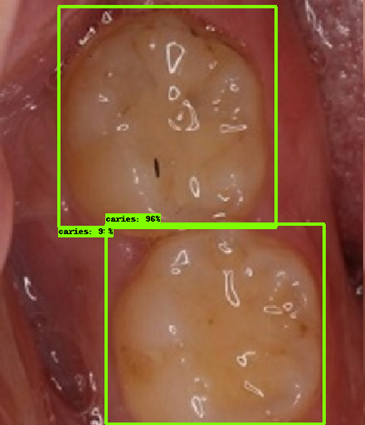

| 모델예측 | 정답 |

|---|---|

![]() |

- 인식이 잘 되지 않은 케이스들을 보면, 사람의 눈으로 뚜렷하게 충치로 판단되는 치아를 모델이 잡아내지 못하는 경우도 있었지만, 그보다는 사람의 눈으로도 충치로 분류하기 어려운 경우에 모델역시 잘 분류해내지 못하는 것을 볼 수 있었습니다. 예를 들어, 인식이 잘되지 않은 첫번째 케이스, 세번째 케이스를 보면 정답지에는 충치 치아로 분류되어 있지만, 사람이 한눈에 보기에도 충치라고 판단하기 어려운 사진들이었습니다. 이러한 경우에 모델은 잘 잡아내지 못하고 있습니다.